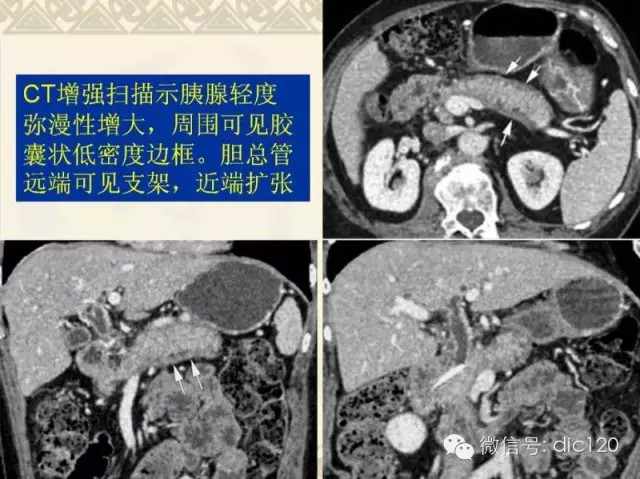

自身免疫性胰腺炎的CT诊断